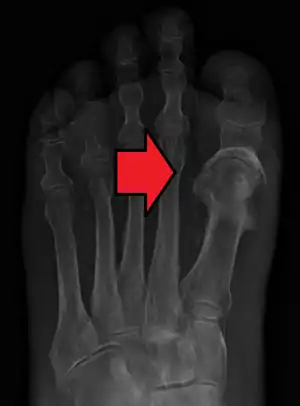

| Microscopic section of the lungs showing a blood vessel with fibrinoid material and an empty space indicative of the presence of lipid dissolved during the staining process. Haematoxylin and eosin stain | |